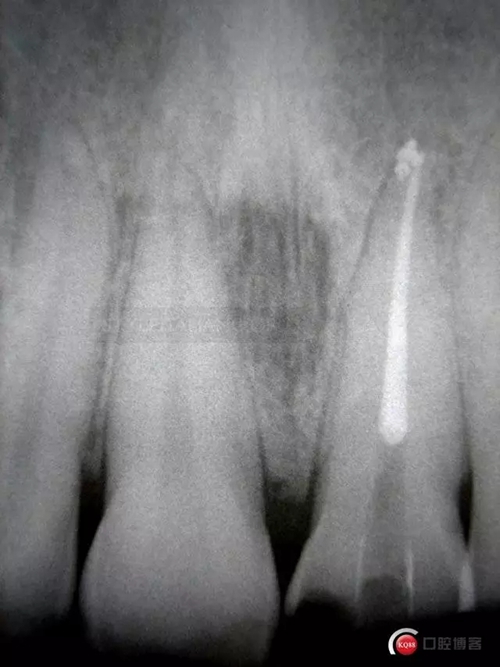

The control x-ray shows emergency profile modification on tooth 2.1 and restorations sealing even if composite overlays are quite radio transparent

875993.jpg